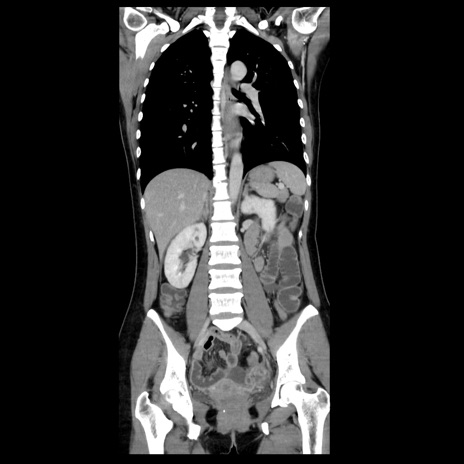

症例39(冠状断像)

【症例】40歳代女性

【主訴】上下腹部痛

【現病歴】2日目から下腹部痛あり。夜間は痛みで眠れなかった。昨日より上腹部痛と下痢が出現。臥位で痛みは軽快したため、休んでいた。本日になって臥位でも立位でも痛みが強くなってきたため救急要請。

【既往歴】子宮内膜症

【身体所見】部:平坦・軟、左上下腹部に圧痛あり、反跳痛あり。

【データ】WBC 21800、CRP 26.78

CT